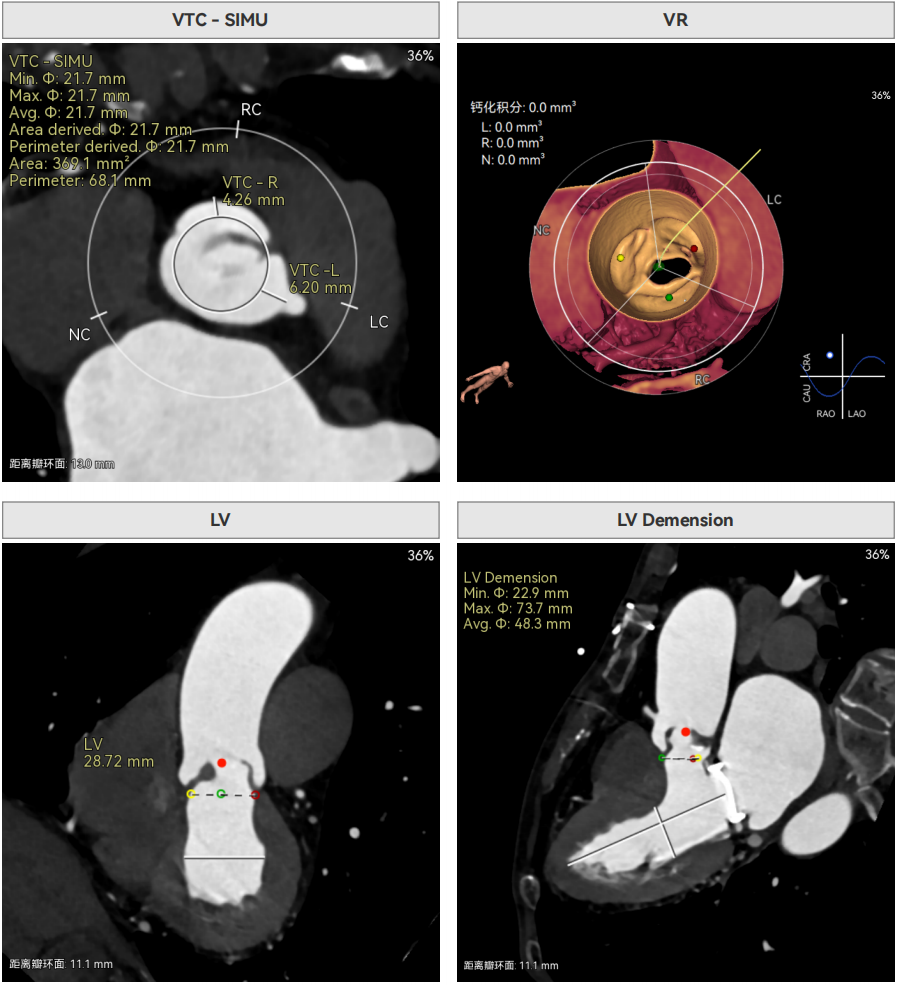

CT报告提示

主动脉瓣环周长径21.4mm,小瓣环,LVOT直筒型结构;风湿性三叶瓣,三窦交界粘连,限制最窄预估周长17.5mm。心脏角度41.8,瓣上限制重,无冠脉风险。

左室较小、有一定循环崩溃风险,SMVR植入术后,距离与角度可,植入过深可能影响二尖瓣,需精准操作控制植入位置。

外周入路无明显迂曲,胸腹主散在钙化。双侧股动脉内径小,右股最窄4.4mm,左股最窄4.1mm,需使用内联鞘版本尝试通过,右股中分叉。主动脉弓角、弓距可。

• 小瓣环伴重度瓣上限制,PPM(患者 - 假体不匹配)风险突出:患者主动脉瓣环周长衍生直径仅 21.4mm,LVOT 直径 21.7mm,且存在三窦交界融合,瓣上 12mm 处限制约 17.5mm,瓣上空间狭窄对瓣膜径向支撑力、有效瓣口面积(EOA)要求严苛,瓣膜选择不当极易导致 PPM,引发术后跨瓣压差过高、血流动力学恶化。

• SMVR 术后特殊解剖,二尖瓣受侵风险高:患者为 SMVR 术后,机械瓣与原瓣环距离仅 5mm,夹角 120°,若介入瓣膜植入过深,极易干扰二尖瓣开合功能,引发新的心脏瓣膜功能异常,对瓣膜释放的定位精度提出微米级要求。